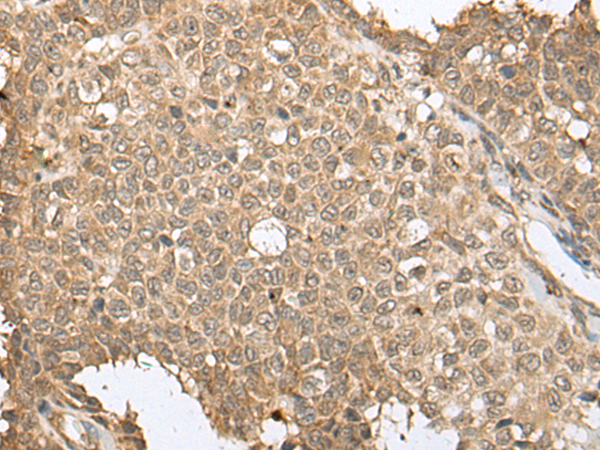

分类: 科研抗体货号: P09414别名: DECRD; MNADK; NADKD1; C5orf33应用: WB,IHC反应种属: Human, Rat